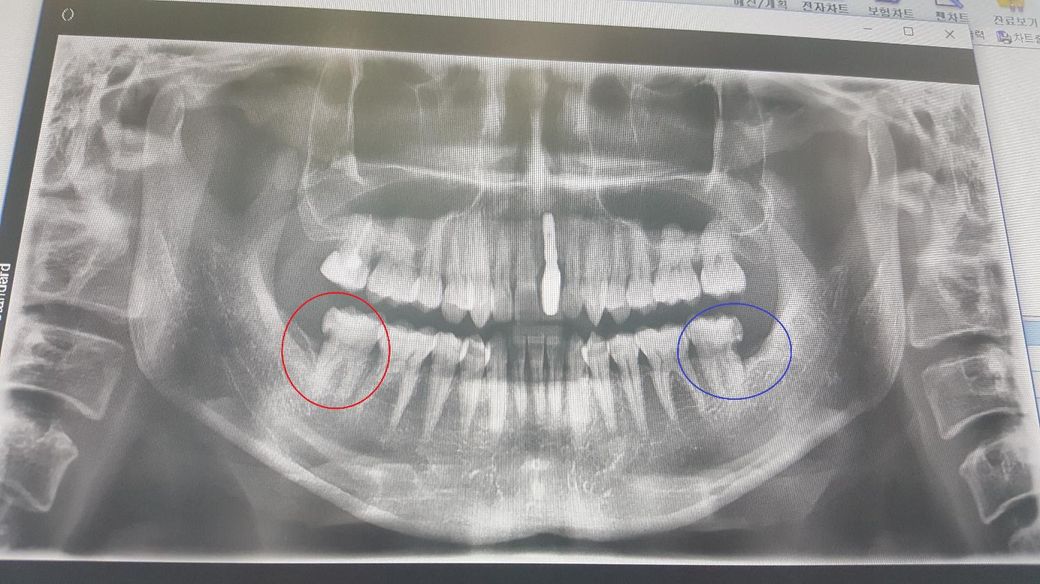

파란 원과 빨간 원 모두 매복 사랑니로 인해 생긴 충치입니다.

파란 원은 현재 신경치료 1번 진행했구요 빨간 원은 아직입니다.

의사선생님께서는 둘 다 신경치료 후 크라운 씌워야 한다고 하셨습니다.

빨간 원 쪽 치아도 꼭 해야하는 상태인가요?

파란색 동그라미에 있는 치아의 경우에는 충치가 상대적으로 깊어 보입니다. 충치를 제거하고 신경이 노출이 되면은 신경 치료 가능성이 있습니다.

빨간색 원 안에 있는 치아의 경우에는 뒤쪽으로 충치가 있기 때문에 이 부분을 일반 치과 재료로 메꾸기가 힘든 위치입니다. 따라서 크라운 치료를 받는 것이 좋습니다.

사진에 보이는 부분은 잇몸안쪽이고 접근하기가 쉽지 않습니다. 뿌리쪽 충치라 일반적으로 크라운이나 신경치료후 크라운 치료를 합니다.

1. 신경에 가깝게 깊은 충치가 있어 신경치료는 불가피합니다.

2. 신경치료를 한 치아는 약해져 있는 상태이고, 신경치료를 하는 과정에서 구멍을 뚫기 때문에 이 구멍으로 주된 감염경로가 됩니다. 레진으로만 막아두는 것보다는 크라운을 씌워 완전히 밀봉을 해주어야 합니다.